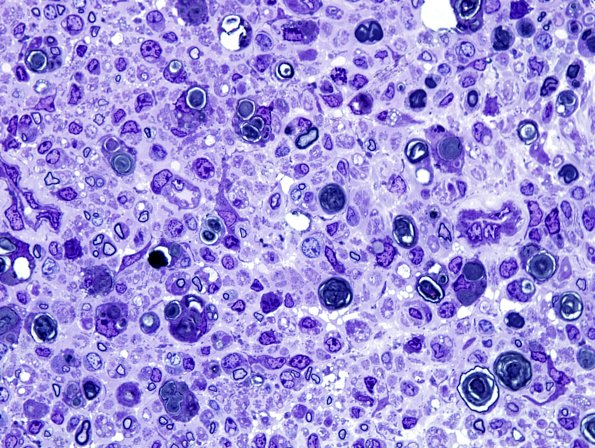

28A1-5 Mouse constriction injury ~10 days following sciatic nerve constriction.---- Various magnifications showing numerous Schwann cells and macrophages admixed with myelin debris.